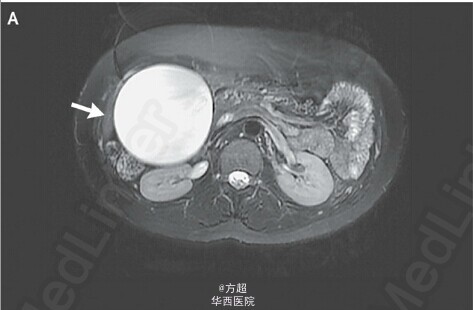

31岁青年女性,因间断发作右上腹疼痛就诊,自诉可于右侧腹部扪及缓慢长大包块;自诉无黄疸、发热、体重下降等情况,肝酶等实验室检查无异常,腹部超声未见异常,腹部MRI提示胆囊扩张17*8cm(如图A、B),但是并未发现胆管结石,胆管外源性受压以及胆管畸形;告知风险后予以腹腔镜下胆囊切除术,术中证实胆囊扩张积水,余无异常发现;术后患者症状逐步缓解。André Brito Queiroz, M.D., and Jocielle Santos de Miranda, M.D.N Engl J Med 2011; 364:e43;原文链接:http://www.nejm.org/doi/full/10.1056/NEJMicm1000943